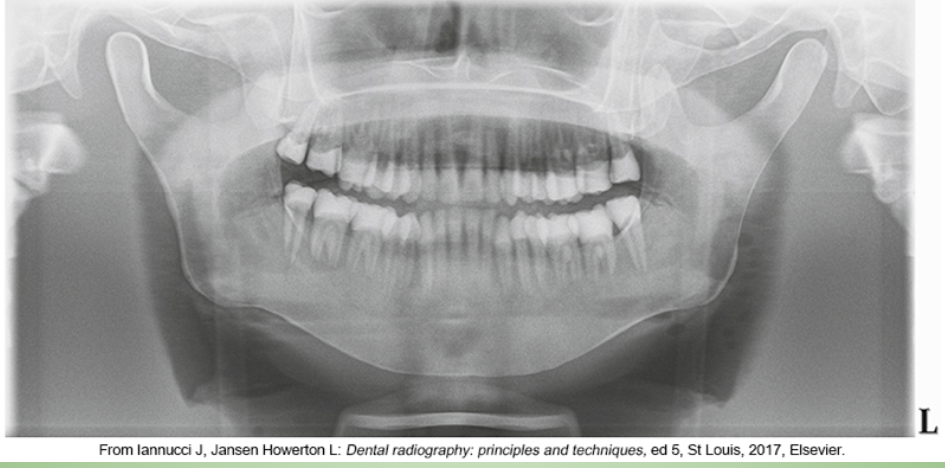

whats the problem

chin too low